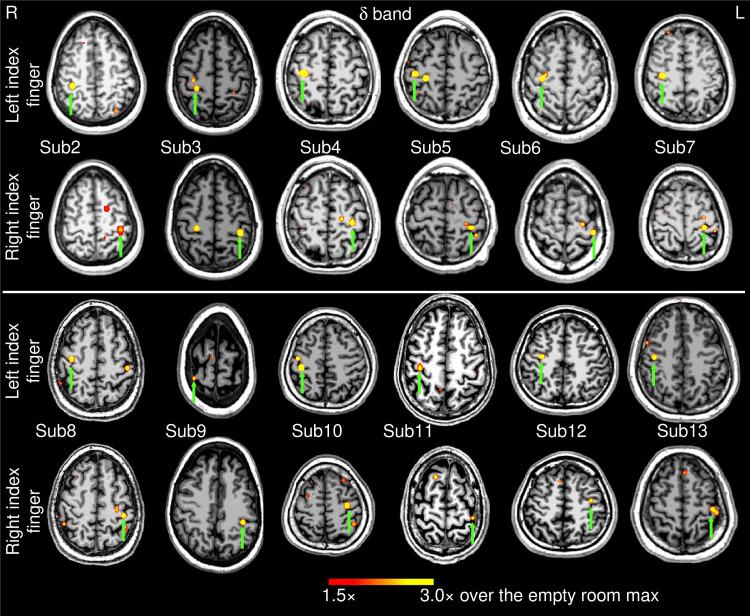

Magnetoencephalography (MEG) is a non-invasive functional imaging technique for pre-surgical mapping. However, movement-related MEG functional mapping of primary motor cortex (M1) has been challenging in presurgical patients with brain lesions and sensorimotor dysfunction due to the large numbers of trials needed to obtain adequate signal to noise. Moreover, it is not fully understood how effective the brain communication is with the muscles at frequencies above the movement frequency and its harmonics. We developed a novel Electromyography (EMG)-projected MEG source imaging technique for localizing early-stage (-100 to 0 ms) M1 activity during l min recordings of left and right self-paced finger movements (1 Hz). High-resolution MEG source images were obtained by projecting M1 activity towards the skin EMG signal without trial averaging. We studied delta (1-4 Hz), theta (4-7 Hz), alpha (8-12 Hz), beta (15-30 Hz), gamma (30-90 Hz), and upper-gamma (60-90 Hz) bands in 13 healthy participants (26 datasets) and three presurgical patients with sensorimotor dysfunction. In healthy participants, EMG-projected MEG accurately localized M1 with high accuracy in delta (100.0%), theta (100.0%), and beta (76.9%) bands, but not alpha (34.6%) or gamma/upper-gamma (0.0%) bands. Except for delta, all other frequency bands were above the movement frequency and its harmonics. In three presurgical patients, M1 activity in the affected hemisphere was also accurately localized, despite highly irregular EMG movement patterns in one patient. Altogether, our EMG-projected MEG imaging approach is highly accurate and feasible for M1 mapping in presurgical patients. The results also provide insight into movement-related brain-muscle coupling above the movement frequency and its harmonics.

脑磁图(MEG)是一种用于术前脑图谱绘制的非侵入性功能成像技术。然而,对于患有脑损伤和感觉运动功能障碍的术前患者,由于需要大量试验来获得足够的信噪比,对初级运动皮层(M1)进行与运动相关的MEG功能图谱绘制一直具有挑战性。此外,对于运动频率及其谐波以上频率的大脑与肌肉之间的通信效果如何,目前尚未完全了解。我们开发了一种新颖的肌电图(EMG)投影MEG源成像技术,用于在左右自主手指运动(约1Hz)的约1分钟记录期间定位早期(-100至0ms)M1活动。通过将M1活动投影到皮肤EMG信号上而无需试验平均,获得了高分辨率的MEG源图像。我们研究了13名健康参与者(26个数据集)和三名患有感觉运动功能障碍的术前患者的δ(1-4Hz)、θ(4-7Hz)、α(8-12Hz)、β(15-30Hz)、γ(30-90Hz)和上γ(60-90Hz)频段。在健康参与者中,EMG投影MEG在δ(100.0%)、θ(100.0%)和β(76.9%)频段中以高精度准确地定位了M1,但在α(34.6%)或γ/上γ(0.0%)频段中则不然。除了δ频段外,所有其他频段都高于运动频率及其谐波。在三名术前患者中,尽管一名患者的EMG运动模式高度不规则,但受影响半球的M1活动也被准确地定位。总体而言,我们的EMG投影MEG成像方法对于术前患者的M1图谱绘制非常准确且可行。这些结果还为运动频率及其谐波以上的与运动相关的脑-肌肉耦合提供了见解。